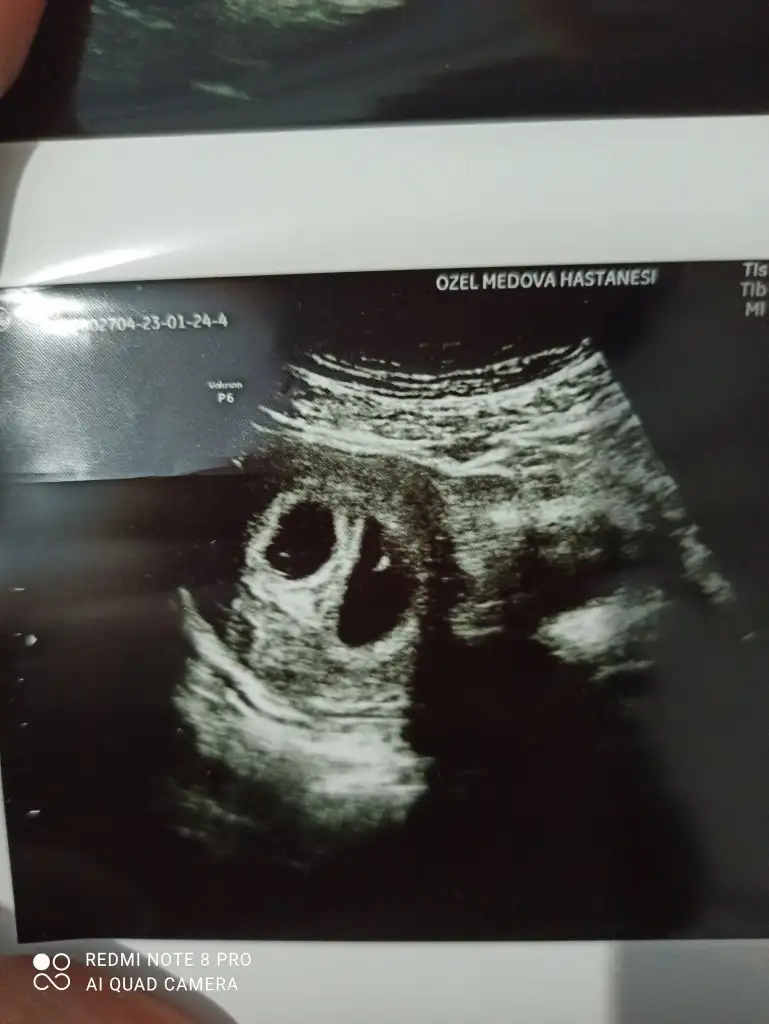

Merhaba 7 haftalık vajinal ultroson fotoğrafıKızlar ultrason fotolarınızı atın 6 ve 7.hafta ya da 11. 12. 13. Hafta yorumlayayim. Amacım kesin bilmek değil net bi şey söyleyemem ancak ultrason net olursa daha iyi olur :)

Ben erkek diyorum Canm. Masallah sanki şekli semali belliMerhaba 7 haftalık vajinal ultroson fotoğrafışu an 16. Haftadayim 17 de kontrole gidicem cinsiyeti söylerse bu sefer doktor yazarım. Teşekkür ederim şimdiden tahmin için

Rahmin ne kdr farklı canım kistin falan mı varMerhaba 7 haftalık vajinal ultroson fotoğrafışu an 16. Haftadayim 17 de kontrole gidicem cinsiyeti söylerse bu sefer doktor yazarım. Teşekkür ederim şimdiden tahmin için

Canım normalde rahim beyaz olur böyle dumanlı gbii falan olur pürüzsüz düşün ama sende sanki balık kafası var gbi Bi şekil yanında irili ufaklı Bi sürü kese gibi küçük şeyler var bunlar genelde kisttir ordan cıkarım yaptımBenim genelde kist oluşuyor çok sık ama bı sıkıntı olmayacağı için bir şey demiyor doktorlar. Hatta doktorum tedaviyle mi oldu bebek diye sordu. Ama çok şükür öyle bı problemim hiç olmadı düşündüğümüz ay direk oldu ilk gebeliğim de buda. Nerden anlıyorsunuz ya ben anlayamıyorum doktor da söylediği için merak ettim ilk hamileligim de de doktor tedaviyle olduğumu düşünmüştü